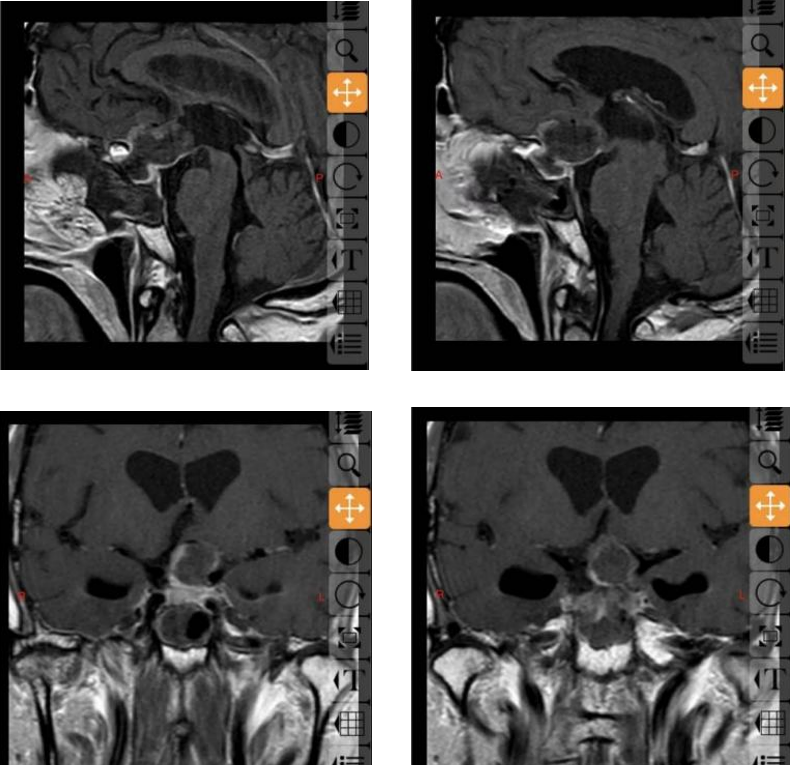

68岁的邓大叔是一位饱受垂体瘤困扰的“老战士”,11年前他经鼻行垂体瘤手术,几年后垂体瘤复发再次通过伽马刀治疗,经过两次历练后的他以为之后就可以高枕无忧,没想到近期的复查报告显示肿瘤“卷土重来”,且这次情况远比之前“棘手”,复发的肿瘤不仅从鞍内生长到鞍上,还与大脑的“生命线”——前交通动脉以及掌管意识记忆的三脑室底粘连紧密,甚至朝一侧颈内动脉上方生长,就像一颗埋在大脑深处的“不定时炸弹”,位置险要,结构复杂。

最终,由张治国医生主刀,为邓大叔顺利实施了这例高难度的经鼻蝶微创手术,肿瘤被完整、精准地切除,紧密粘连的前交通动脉及三脑室底均保护完好。

术后邓大叔也恢复得很快,头痛等不适症状消失,精神状态良好,他对手术效果非常满意,这次成功的“精准拆弹”,为他扫清了安享幸福晚年的最大障碍。